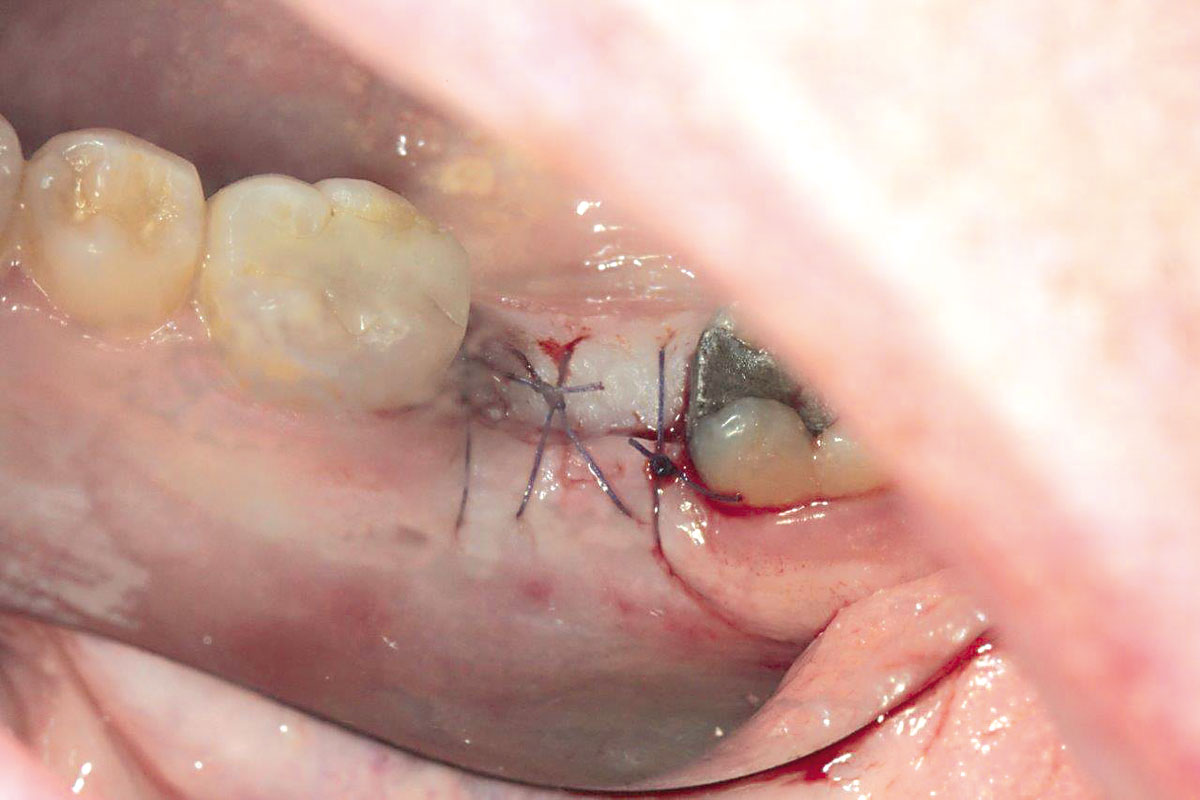

botiss cerabone® & collagen fleece for immediate implantation - Clinical case by Dr. D. Jelušić

Clinical situation before extraction and implantation